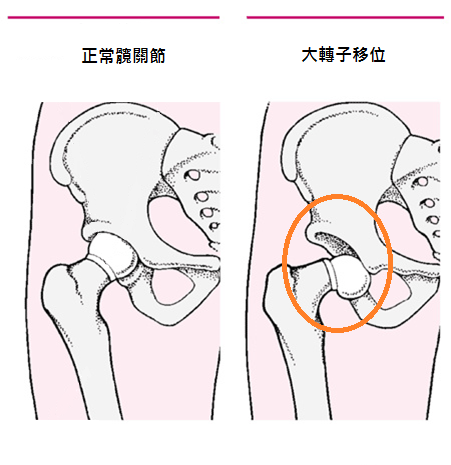

2. 股骨移位

大腿骨尾端與骨盆連接的關節移位,也會造成梨形身材的體型;通常會發生在走路姿勢不正確、從小體弱的女生、或是懷孕時缺鈣的媽媽等等。股骨移位的樣子大概是像下圖:

這類梨形身材的人,有時候走路、下蹲或是做運動的時候,骨盆與大腿連接的問至會出現喀啦的聲音,因為股骨大轉子沒有完整的卡在骨盆的凹槽裡,無法好好的在正常軌道上活動與運動,到了一定的角度就會滑落、發出聲響。